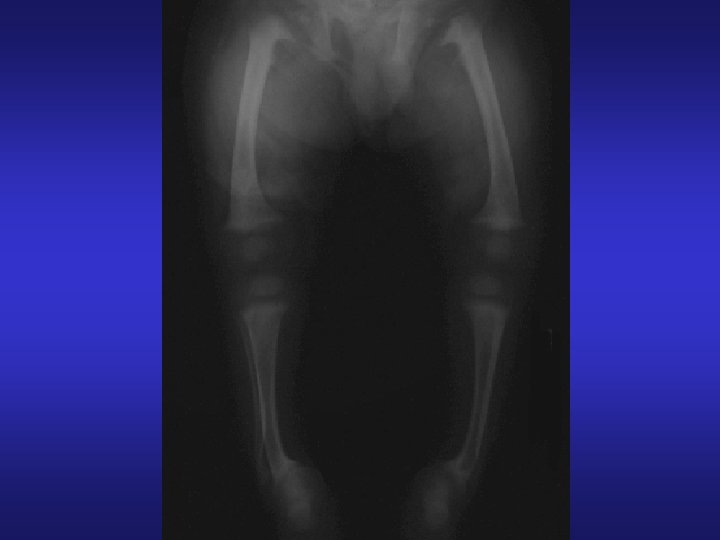

Bone Disorders Osteomalacia: Loss of bone salts but not collagen due to poor diet, decreased absorption of calcium, and vitamin D deficiency. Basically a demineralization of bone Example: Rickets in young children